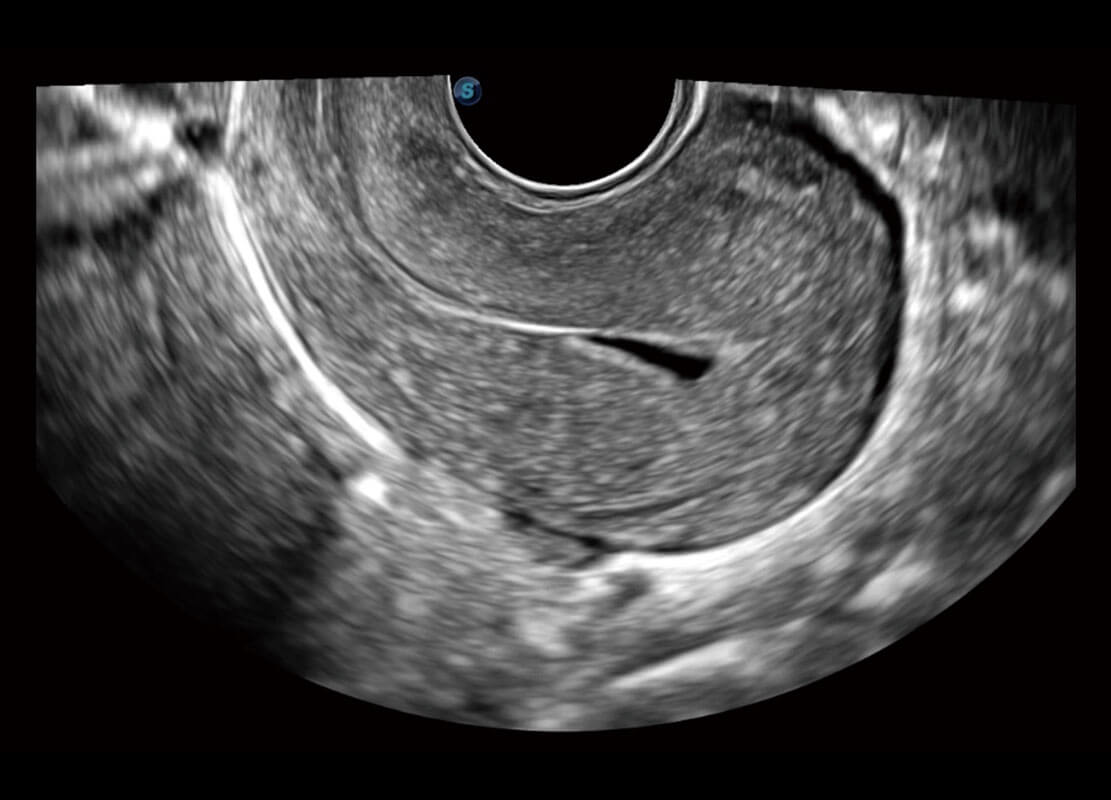

腔内妇科-卵巢

P60优异的图像质量搭载专科探头,在妇科基础疾病的诊断、卵泡生长的监测、输卵管通畅情况的判别等方面为您提供生殖应用方案。